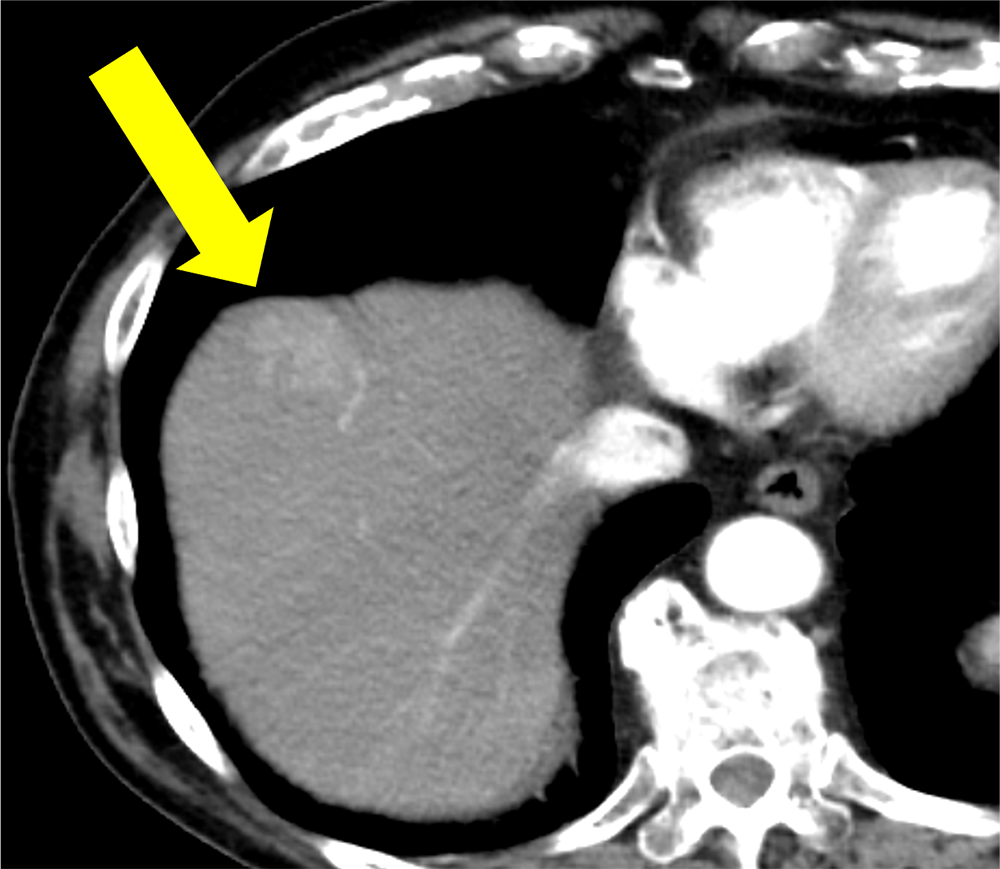

アルコール性肝障害の既往あり。人間ドックの腹部超音波検査で肝腫瘤を指摘され、撮像された造影CTで肝S8の多血化肝細胞癌と診断とされた。単発の病変であり、腹腔鏡下肝S8亜区域切除術が施行された。術後3日目に腹壁瘢痕ヘルニアによる小腸閉塞があり、イレウス解除および腹壁瘢痕ヘルニア修復術が施行された。以降は腫瘍の再発なく経過観察を継続している。

当該疾患の診断における造影CTの役割

CT技術や撮像プロトコル設定について

今回の造影CTでは造影剤注入を一定速度で注入するのではなく、注入速度を連続的に減少させながら注入する可変注入を用いている。造影剤の総量や注入時間は変化させず、注入速度のみを変化させるため、通常注入と比べて注入開始時の速度は上昇し、終了時の速度は低下する。つまり注入の前半により多くの造影剤を注入し、後半に注入される造影剤は減少する。通常注入を行った場合、動脈相の撮像時点では注入された造影剤の一部は病変には到達しておらず、多血化の評価に活用されている造影剤量は想定よりも少ない可能性があるが、可変注入で注入前半に多くの造影剤を注入することで、より多くの造影剤を多血化の評価に活用することができる。また従来の注入法と比べて可変注入法では大動脈の造影効果のピークが前倒し、ピークのCT値も上昇する。これらにより多血化肝細胞癌の造影効果が上昇し、腫瘍と背景肝のコントラストが上昇する。また従来法では早期動脈相では腫瘍の造影効果は通常得られないが、可変注入法では早期動脈相から腫瘍の造影効果が得られ、まだCT値が上昇していない背景肝とのコントラストが良好となり、多血化肝細胞癌の検出能を向上させる可能性がある。